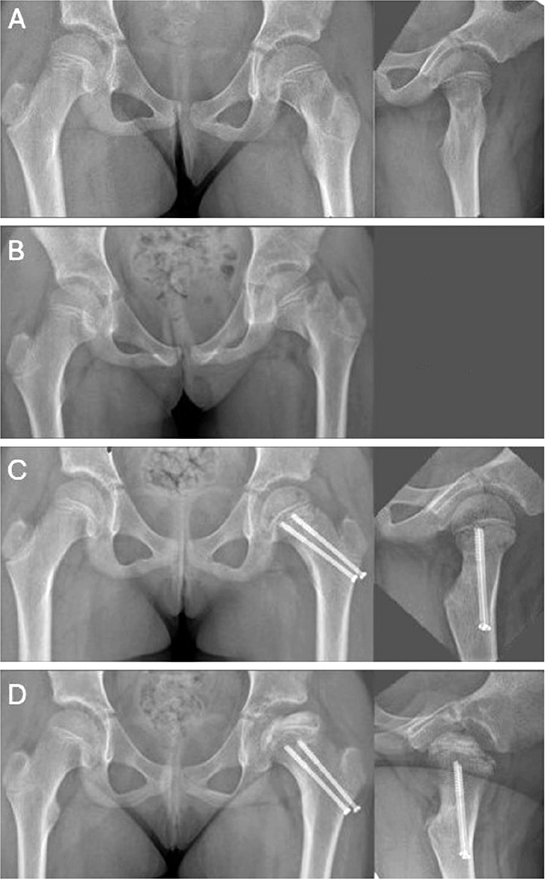

Pediatric collum and trochanteric fractures are currently approached in good time, with an emphasis on anatomic reduction and internal fixation, by open reduction, if necessary, to mitigate severe complications such as AVN, coxa vara, and nonunion [4,16,22]. However, a uniform management strategy is yet to be defined. In our study, we encountered a failure of initial nonoperative management of a collum facture, leading to AVN (Figure 4). For us, this emphasizes the importance of internal fixation even in non-displaced femoral collum fractures.

Figure 4. (A) Primary radiographs showing a non-dislocated Delbet II fracture in an 8-year-old girl. (B) Loss of alignment at 10 days’ follow-up. (C) Ratliff type 1 AVN at 3 months post-injury. (D) AVN at 11 months post-injury.